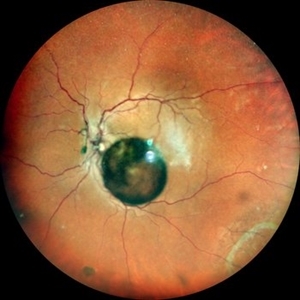

Vitreous Cyst Vitreous CystOct 16 2022 by Pramod Kumar Suman, MBBS, MD Fundus photograph of an 63-year-old male with a floating vitreous cyst. Photographer: Pramod Kumar Suman, Retina Foundation, Ahmedabad Imaging device: Mirante Condition/keywords: vitreous cyst